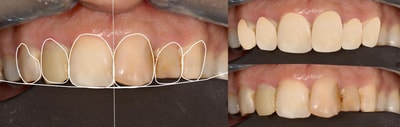

Cas numero 1 :

Situation Initiale

Etude du cas et proposition

Cas terminé

Cas numero 2 :